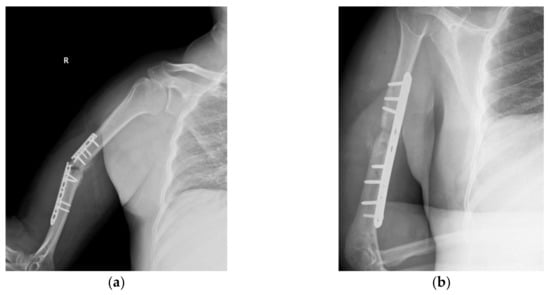

2.1. Clinical Details and Circumstances of Implant Failure